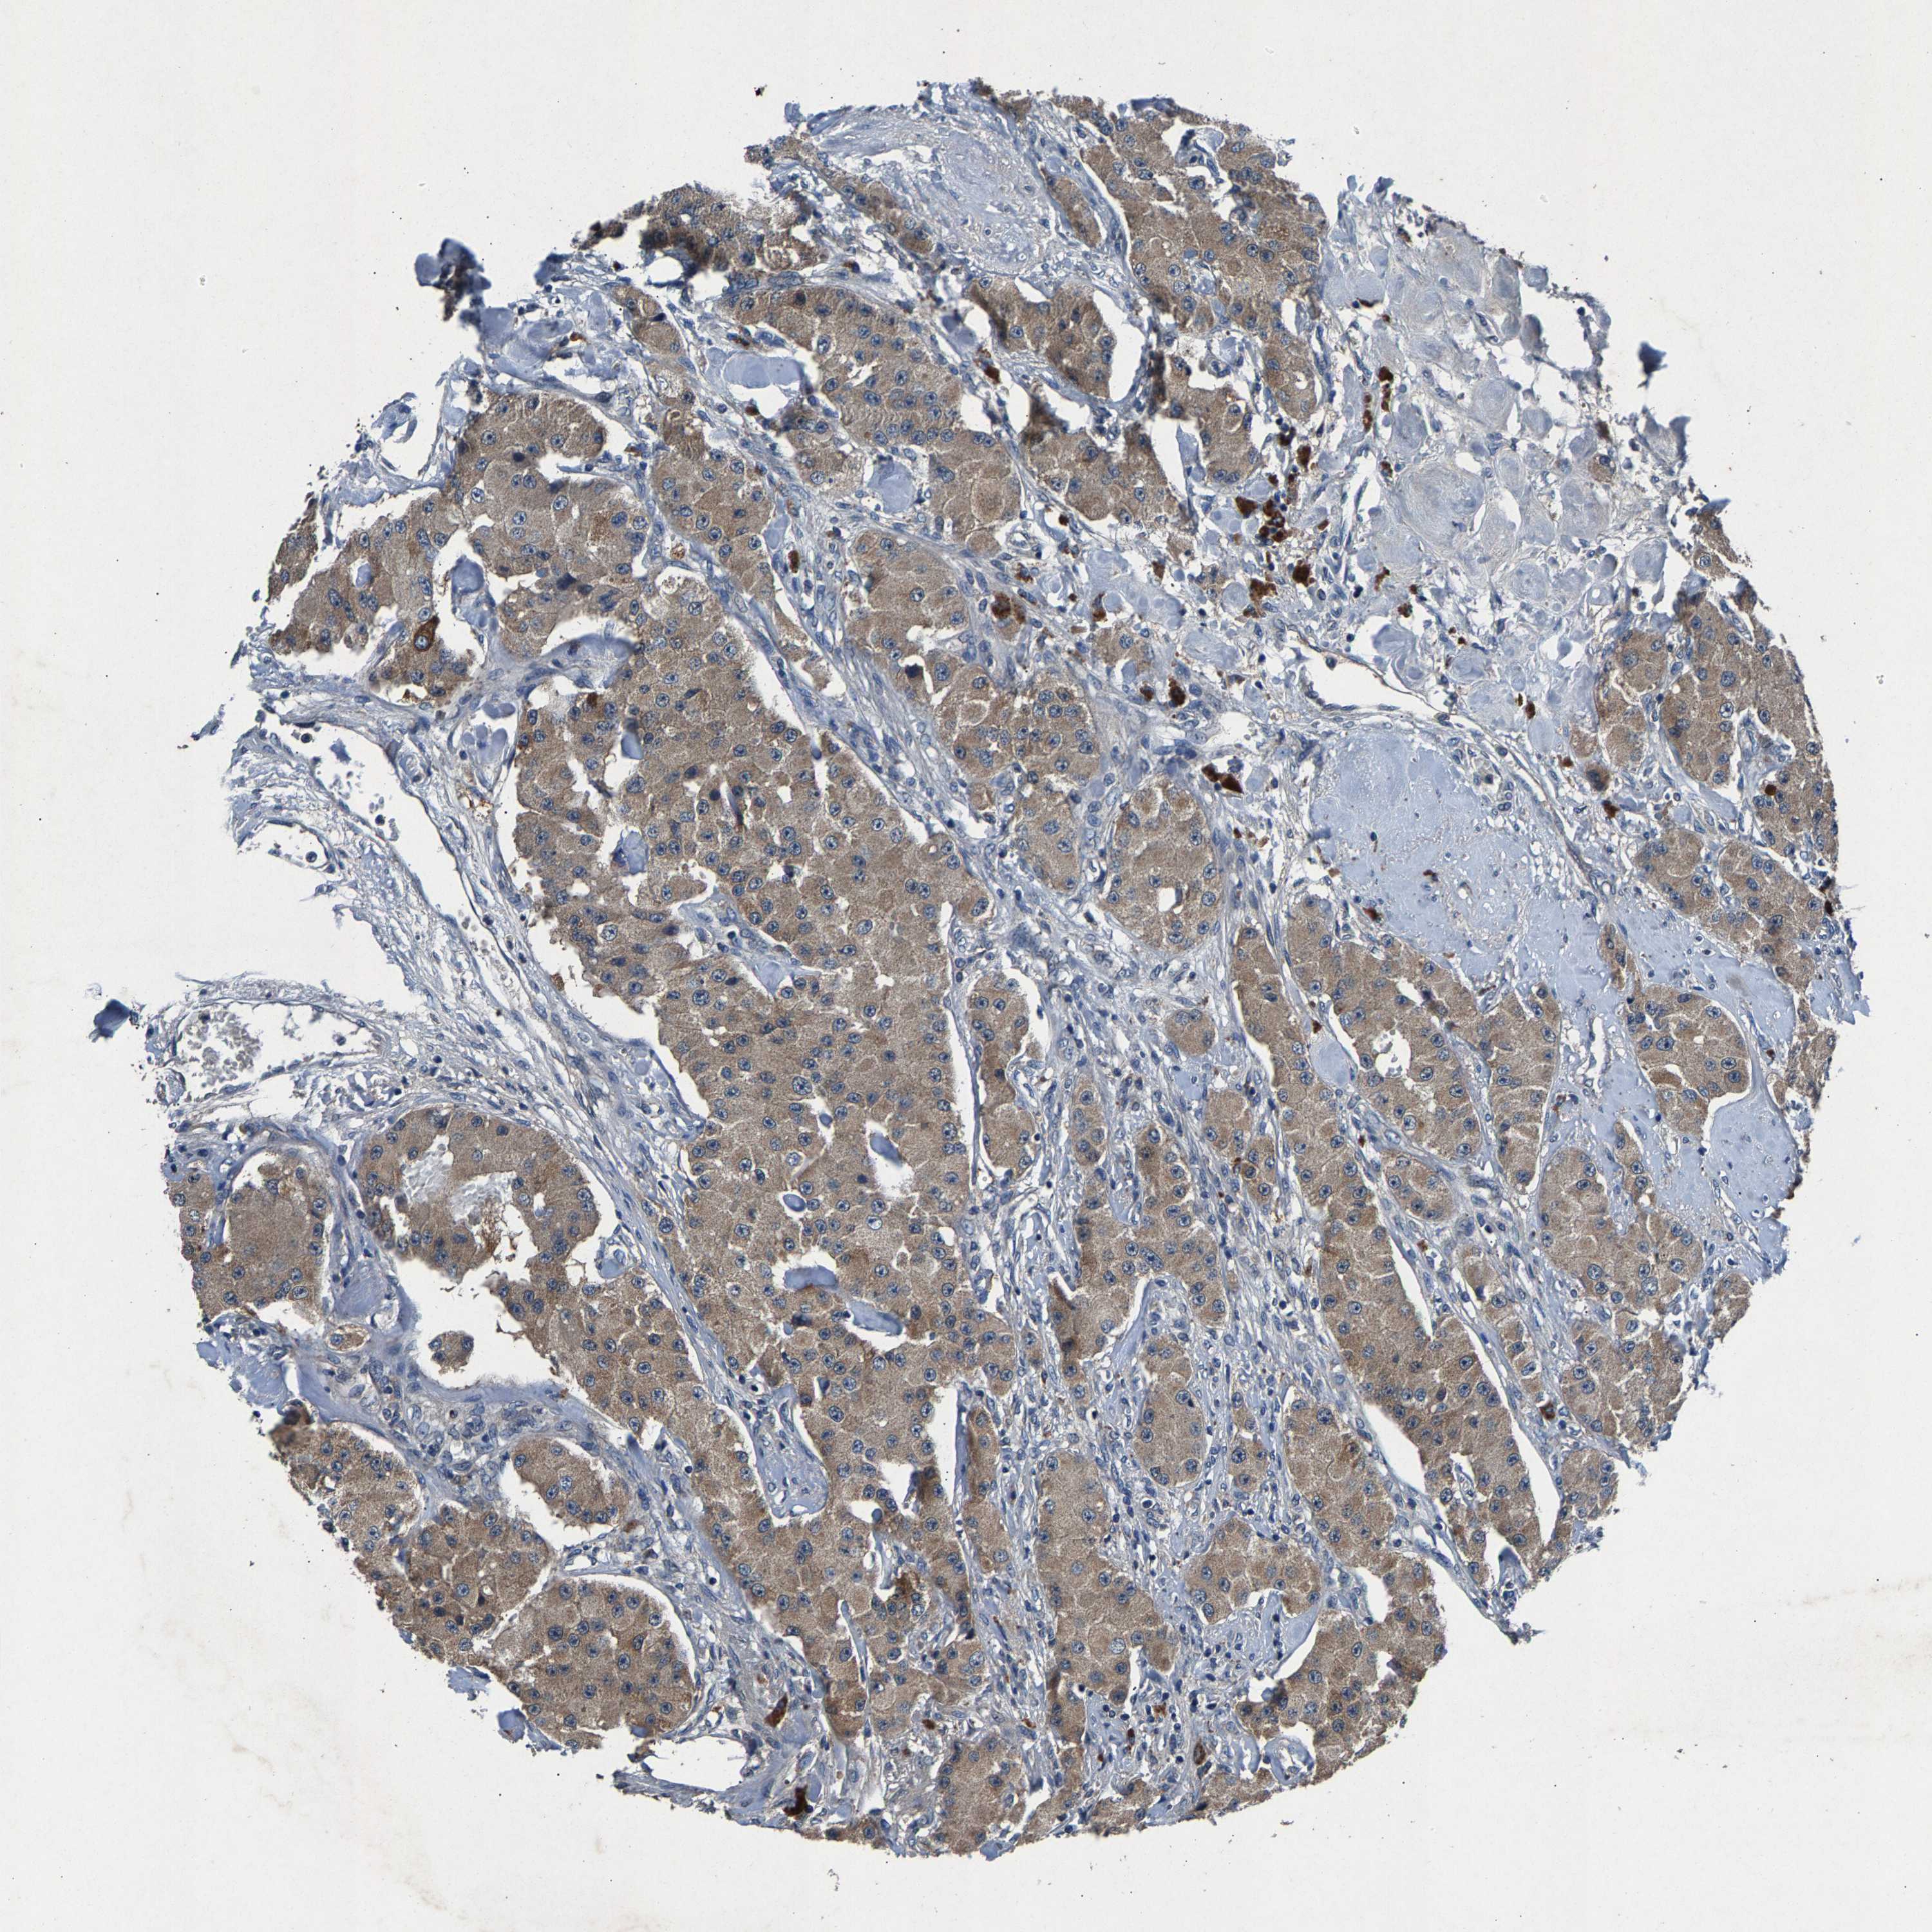

CARCINOID - Protein expressioni

A mouse-over function shows sample information and annotation data. Click on an image to view it in a full screen mode. Samples can be filtered based on level of antibody staining by selecting one or several of the following categories: high, medium, low and not detected. The assay and annotation is described here.

Antibody stainingi

Antibody staining in the annotated cell types in the current human tissue is reported as not detected, low, medium, or high, based on conventional immunohistochemistry profiling in selected tissues. This score is based on the combination of the staining intensity and fraction of stained cells.

Each image is clickable and will lead to virtual microscopy that enables deeper exploration of all samples and also displays staining intensity scores, fraction scores and subcellular localization as well as patient and tissue information for each sample.

Antibody HPA021294

Staining

High

Medium

Low

Not detected

Intensity

Strong

Moderate

Weak

Negative

Quantity

>75%

75%-25%

<25%

None

Location

Nuclear

Cytoplasmic/membranous

Cytoplasmic/membranous,nuclear

Carcinoid, malignant, NOS

Carcinoma, NOS